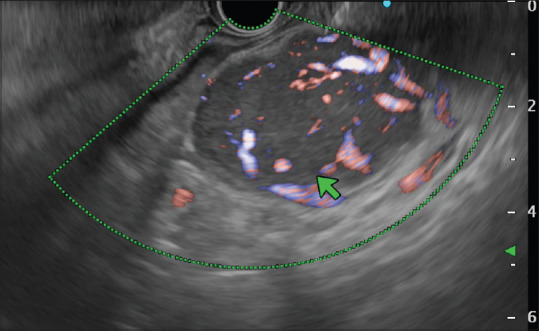

Castleman disease is a nonmalignant, lymphoproliferative disorder. Unicentric disease type involves a single enlarged lymph node or nodal regions, and multicentric disease involves multiple lymph node site involvement. We present a case of 26-year-old young female presented to outpatient with complaint of generalized weakness and abdominal pain for last 2 months. Her imaging included positron emission computed tomography which showed soft-tissue mass along the body of pancreas. Endoscopic ultrasound done showed nodal mass with extensive calcification and doppler endoscopic ultrasound showing arborising vessels. Fine needle aspiration cytology (FNAC) and biopsy taken showed lymphoid cells and diffuse hyaline material. After suboptimal response to chemotherapy regimen, she underwent open laparotomy and excision of the retroperitoneal mass.

Castleman病是一种非恶性淋巴增生性疾病。单中心性疾病类型涉及单个肿大的淋巴结或淋巴结区域,多中心性疾病涉及多个淋巴结部位。我们报告了一例26岁的年轻女性,在过去的两个月里,因全身无力和腹痛而门诊就诊。她的成像包括正电子发射计算机断层扫描,显示胰腺体部的软组织肿块。内窥镜超声检查显示结节性肿块伴广泛钙化,多普勒内窥镜超声波检查显示树枝状血管。细针抽吸细胞学检查(FNAC)和活检显示淋巴细胞和弥漫性透明质。在对化疗方案反应不佳后,她接受了剖腹手术和腹膜后肿块切除术。